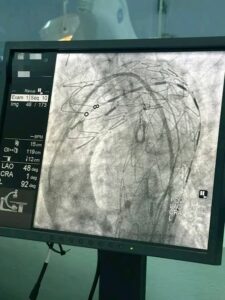

ما تحقق في المستشفى الجهوي بمنزل بورقيبة ليس مجرد “عملية ناجحة”، بل مؤشر واضح على تحوّل تدريجي داخل المنظومة الصحية العمومية في تونس. إجراء أول عملية لتركيب دعامة للأبهر الصدري النازل (Endoprothèse aortique) لمريضة في سن 58 سنة يمثل قفزة نوعية في مستوى التدخلات القلبية خارج المراكز الجامعية الكبرى.

الأهم من ذلك أن هذه العملية تؤكد أن قاعات القسطرة في المستشفيات العمومية لم تعد مجرد فضاءات للتدخلات التقليدية، بل أصبحت قادرة على احتضان إجراءات معقدة كانت إلى وقت قريب حكرًا على مؤسسات محدودة. وهذا يطرح سؤالًا مباشرًا: هل نحن أمام بداية إعادة توزيع فعلية للخدمات الصحية المتقدمة في تونس؟